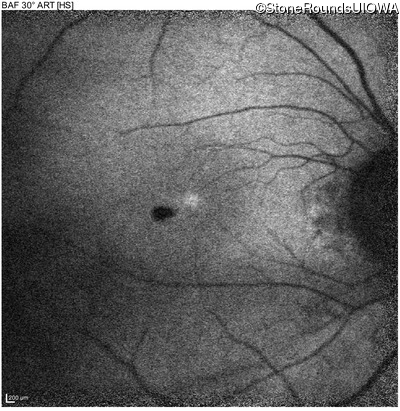

Blue Autofluorescence - Left - 20/40 sc

Exemplar